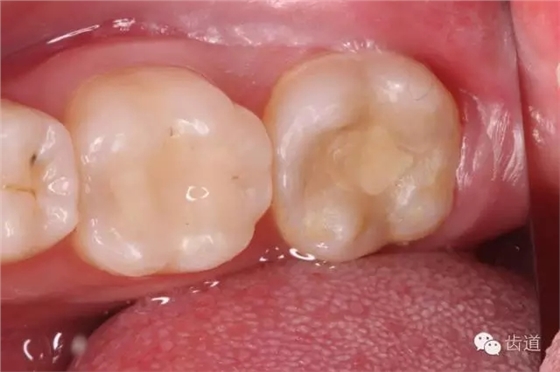

檢查:術(shù)后半年回訪,37牙體及合面嵌體未見(jiàn)缺損及裂紋,邊緣密合,未探及繼發(fā)齲,探痛-,叩痛-,松動(dòng)-,冷水刺激痛-,未探及牙周袋及附著喪失,牙齦無(wú)紅腫,X線片檢查示根尖周膜連續(xù)性恢復(fù),根尖周透射影消失。

1. 術(shù)后半年口內(nèi)照片

2. 術(shù)后半年X線檢查,可見(jiàn)根尖周膜連續(xù)性恢復(fù),根尖周透射影消失